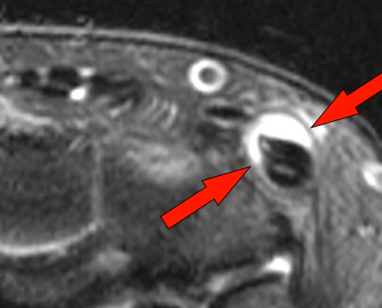

Syndrome de l’Intersection Distale

- Croisement des 2e et 3e compartiment (Extenseurs du Carpe Vs Long Extenseur du Pouce)

- Se fait 4cm plus bas que le tubercule de Lister (bien couvrir sur IRM !)

- Oedème Péritendineux (pas dans la gaine)